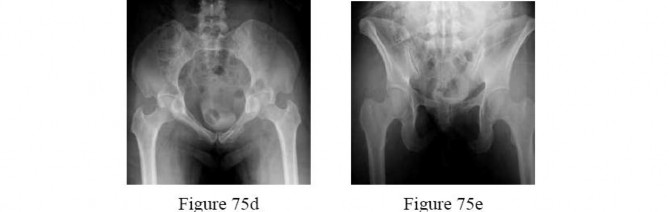

Figure A is an anterior-posterior (AP) radiograph of a 27-year-old male who was a bicyclist struck by a motor vehicle. He was intubated in the field and unresponsive in the trauma slot. Ultrasound of his abdomen is positive for blood and he is brought to the operating room emergently for an exploratory laparotomy. He is found to have ischemic bowel and a grade 4 liver laceration. His lactate is 9.0 mg/dL. Which figure represents the next appropriate step in regard to his pelvic ring injury?

The radiograph exhibits an elevated left hemipelvis with complete sacroiliac disruption, which can be temporized with placement in skeletal traction.

The patient is unstable, as indicated by an elevated lactate level. The most appropriate next step is temporizing skeletal traction to reduce the left hemipelvis.

Langford et al. review the initial diagnosis, evaluation and resuscitation in the management of pelvic fractures. Reduction of pelvic volume can be achieved with pelvic binders and temporizing external fixation for anterior posterior compression (APC) and/or lateral compression (LC) fracture patterns, while skeletal traction can help do the same in vertical shear patterns.

Matullo et al. review the uses of skeletal traction in orthopaedic trauma, where lower extremity skeletal traction can be an efficient, fast, easy way to help reduce pelvic volume in vertical shear injuries, especially when the patient is unstable and not cleared for definitive fixation.

Figure A exhibits an elevated left hemipelvis indicative of a vertical shear injury and complete SI disruption. Figure B is an example of a pelvic binder. Figure C is a pelvic reconstruction plate. Figure D is a schematic of an anterior pelvic external fixator. Figure E is a schematic drawing of a patient in lower extremity

skeletal traction. Figure F is a radiograph exhibiting S1 and S2 sacroiliac (SI) screws.

Incorrect answers:

Answer 1: A pelvic binder would not be helpful in this scenario and actually may worsen the deformity.

Answer 2: Definitive plate fixation of the anterior pelvis will be needed, but only when the patient is adequately resuscitated.

Answer 3: An anterior external fixator may actually do more harm than good as it may require more time than placing skeletal traction, and also have difficulty controlling the posterior pelvis from the front.

Answer 5: Percutaneous SI screws may be placed later, once the patient is resuscitated and stable.